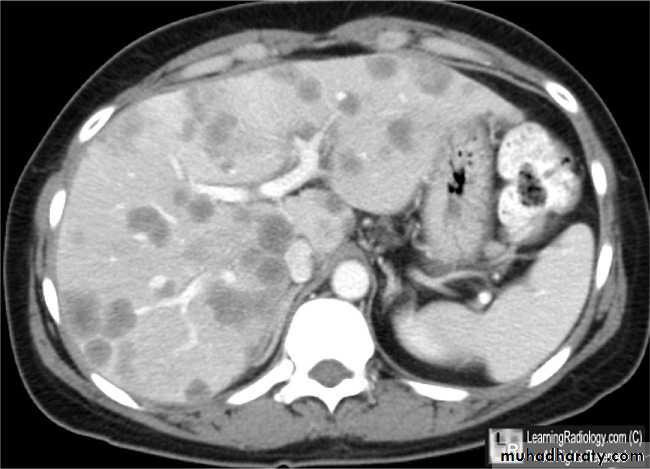

CT scan